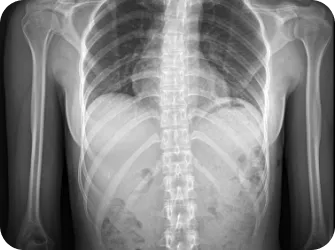

척추 엑스레이 검사

족부 엑스레이 검사

다리길이 엑스레이 검사

모아레 근육 균형 검사

상부경추 1,2번 CT

적외선 체열검사

목 커브와 휘어짐 측정

좌우 어깨 높이와 틀어짐 측정

좌우 골반 수평 및 비틀림 측정

흉추,요추 만곡/ 척추 휘어짐 측정